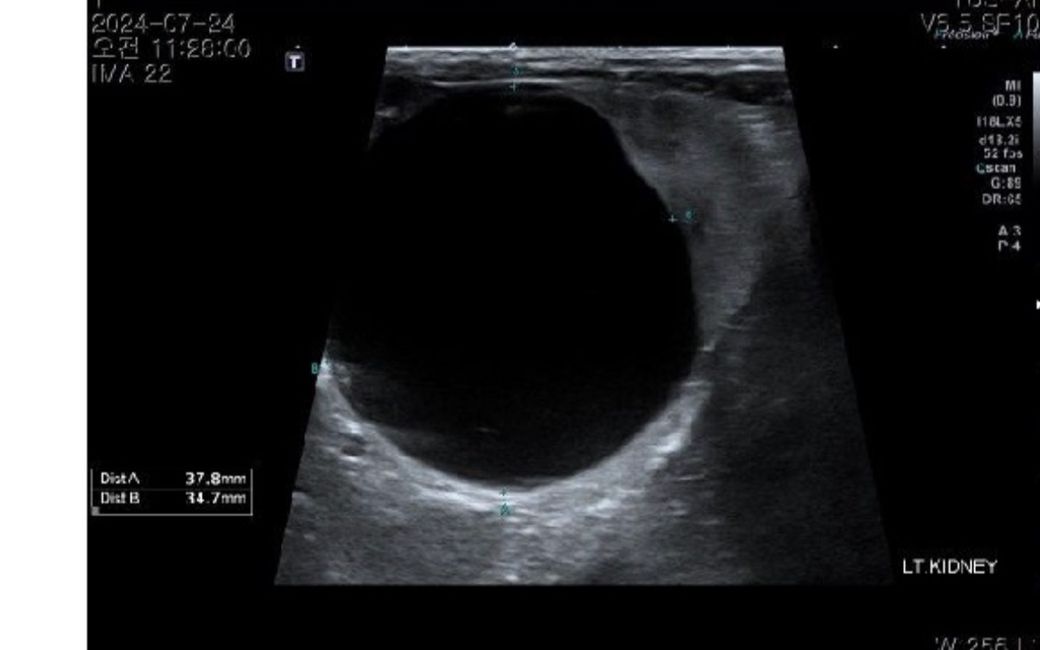

신장낭종이 커서..이거 제거하기는 위험하니까

비장절제하면서 신장낭종경화술 하기로 했습니다

냅두고 사이즈가 줄어드는 경우는 파열하고 자연 치유된 경우 말고는 없습니다. 문제는 파열할때 쇽이 일어나 급사할 수 있기에 치료진행하는것을 추천합니다. 3.7cm 정도면 경화술 예후가 매우 좋은편이기 때문에 하루라도 빨리 경화술로 제것하는것을 추천합니다.